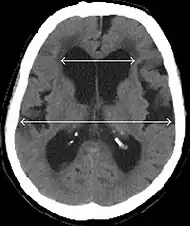

Normal pressure hydrocephalus (NPH), also called malresorptive hydrocephalus, is a form of communicating hydrocephalus in which excess cerebrospinal fluid (CSF) builds up in the ventricles, leading to normal or slightly elevated cerebrospinal fluid pressure. The fluid build-up causes the ventricles to enlarge and the pressure inside the head to increase, compressing surrounding brain tissue and leading to neurological complications. Although the cause of idiopathic (also referred to as primary) NPH remains unclear, it has been associated with various co-morbidities including hypertension, diabetes mellitus, Alzheimer's disease, and hyperlipidemia.[1][2][3] Causes of secondary NPH include trauma, hemorrhage, or infection.[4] The disease presents in a classic triad of symptoms, which are memory impairment, urinary frequency, and balance problems/gait deviations (note: this diagnosis method is obsolete[5][6]). The disease was first described by Salomón Hakim and Raymond Adams in 1965.[7]

- Imaging from magnetic resonance imaging (MRI) or computed tomography (CT) is needed to demonstrate enlarged ventricles and no macroscopic obstruction to cerebrospinal fluid flow. Imaging should show an enlargement to at least one of the temporal horns of lateral ventricles, and impingement against the falx cerebri resulting in a callosal angle ≤ 90° on the coronal view, showing evidence of altered brain water content, or normal active flow (which is referred to as "flow void") at the cerebral aqueduct and fourth ventricle.

MRI scans are the preferred imaging. The distinction between normal and enlarged ventricular size by cerebral atrophy is difficult to ascertain. Up to 80% of cases are unrecognized and untreated due to difficulty of diagnosis.[22] Imaging should also reveal the absence of any cerebral mass lesions or any signs of obstructions. Although all patients with NPH have enlarged ventricles, not all elderly patients with enlarged ventricles have primary NPH. Cerebral atrophy can cause enlarged ventricles, as well, and is referred to as hydrocephalus ex vacuo. For these reasons it's utmost important to note that Evan's index although commonly used in imaging is not very specific for NPH. One recent systematic review and meta-analysis suggests that callosal angle has high diagnostic performance and is commonly used together with Evan's index.[23]